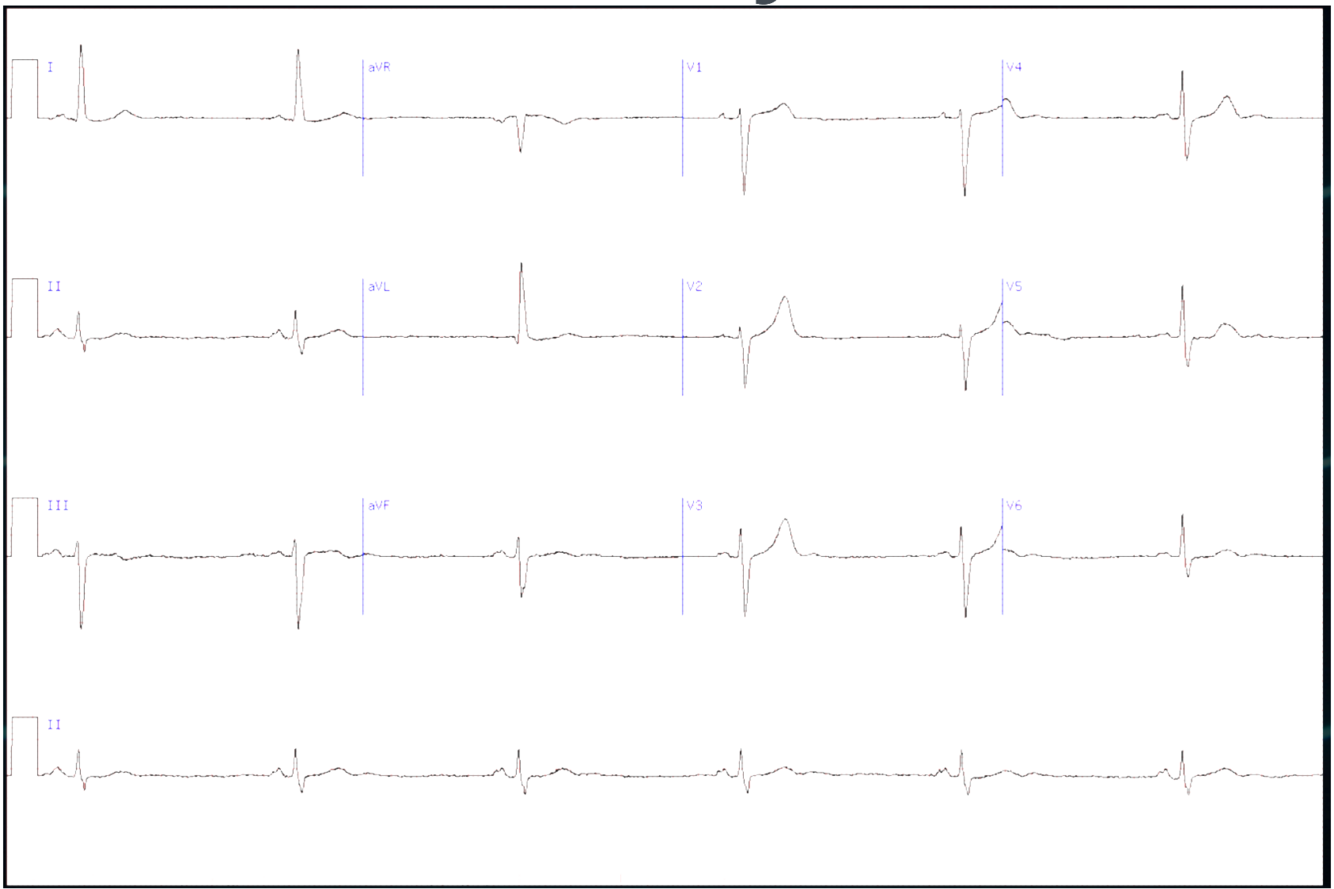

What is this ?

A

1st degree heart block

-PR interval > 200ms (5 small boxes) but every P wave conducted

-Look at I, II, V5 and V6